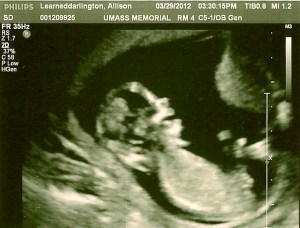

Here are a few of the images (head to the left side of the image, feet to the right side) the wonderful ultrasound technician gave us, she was great, constantly saying “oh, how cute!” But she probably says that with them all, huh? But we’ll pretend ours was extra cute!

Below is Eric’s favorite image. We could see the baby opening and closing his/her mouth and the ultrasound tech was able to capture mouth wide open! Eric said the baby was laughing at all the poking and prodding going on. Or maybe we’ll have a singer!!!